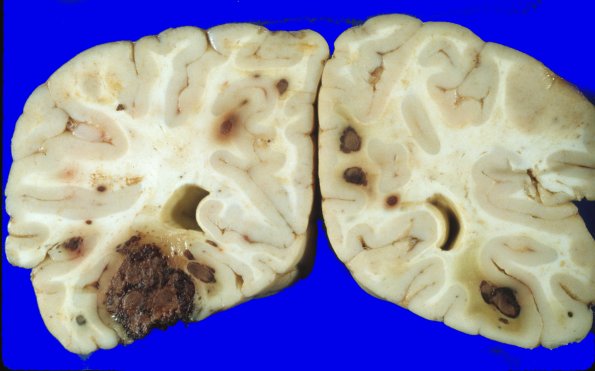

1A5,6 Lesions in this case are typically small; however, the temporal lobe lesion shown in these images is composed of a large aggregate of nodules.